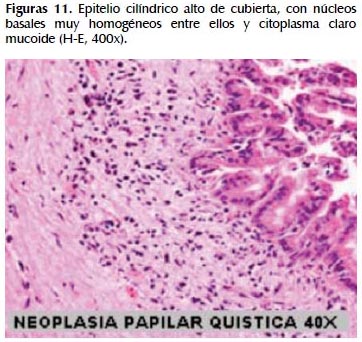

La alteración fundamental en este caso es la presencia de marcada dilatación de los conductos pancreáticos (Figuras 6, 7, 8, 9, 10 y 11) con variable hiperplasia de los conductos menores periféricos.

Los quistes están limitados por células ductales altas, algunas mucinosas, en su mayor extensión dispuestas en una fila. De manera focal se ve proyecciones papilares del epitelio y también focos de erosión con reacción inflamatoria, exudado linfocitario y formación de tejido de granulación.

El resto del parénquima pancreático muestra múltiples focos de autolisis y variable hiperplasia de los ductos.